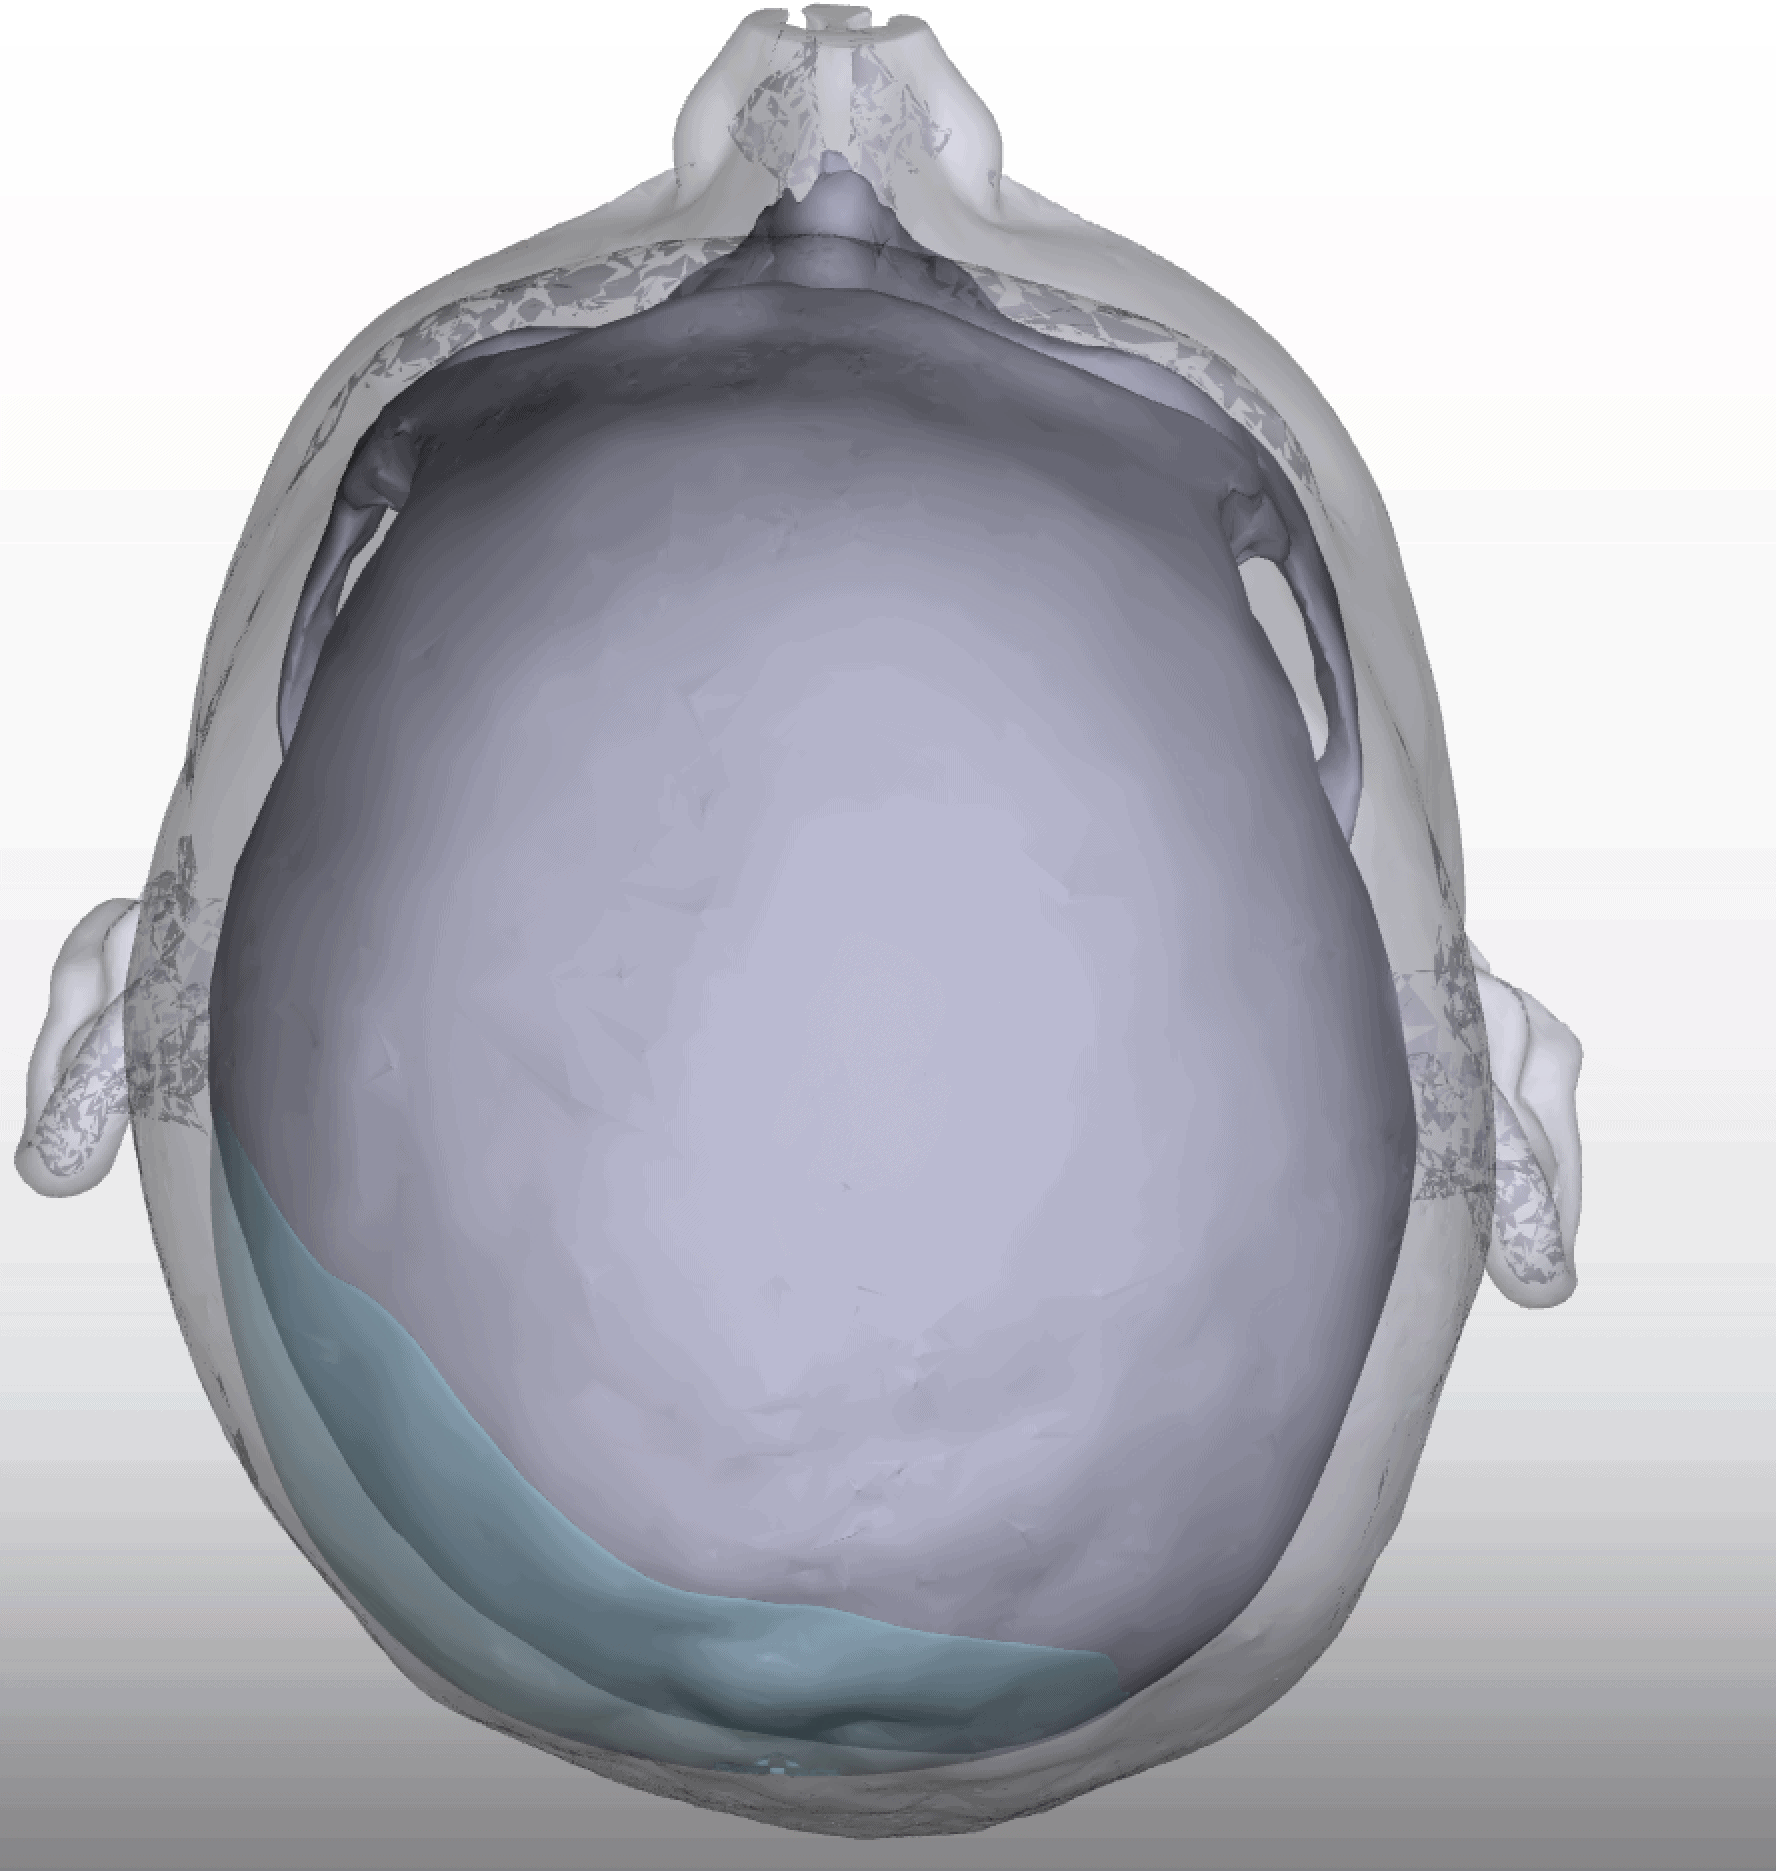

Desire for head shape asymmetry improvement as the final stage of total skull reshaping surgeries. (previous skull implants are in green color)

Placement of custom temporal implant through an incision behind the ear.

Desire for head shape asymmetry improvement as the final stage of total skull reshaping surgeries. (previous skull implants are in green color)

Placement of custom temporal implant through an incision behind the ear.